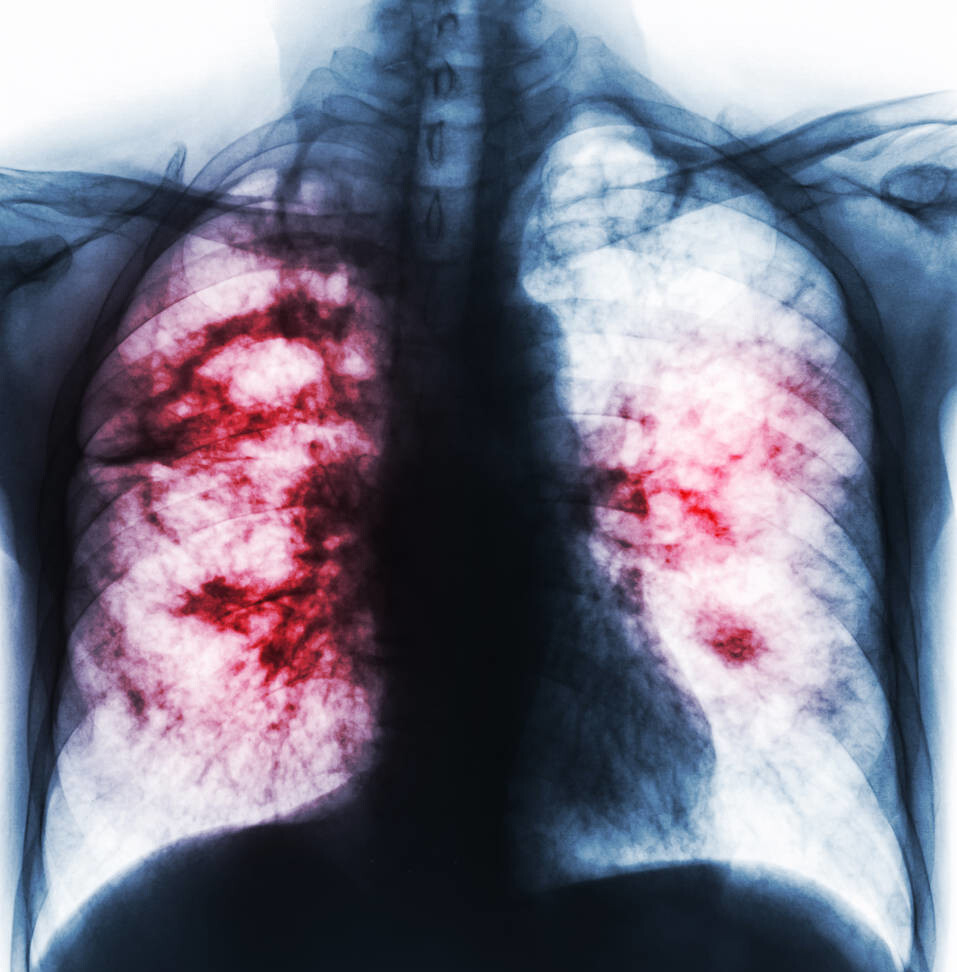

拿过她的片子看了一下 , 瞬间明白是怎么回事 , CT上清清楚楚地显示是“支气管扩张” , 这个病是我国导致咯血的最常见原因之一 , 除了这个排在后三位的分别是结核、肺癌、肺炎 , 其他还有不少疾病会导致咯血 , 有女性甚至和月经周期有关 , 是子宫内膜通过血液流淌到肺导致的 。

支气管扩张的发病原因大部分继发于肺部感染之后 , 比如肺炎、肺结核等等 , 这个疾病是由细菌等微生物导致的 , 这些微生物破坏肺的同时 , 常常破坏气管支气管 , 肺修复能力很强 , 很快就结疤了 , 支气管结不了疤 , 破坏了就会被肺被动的拉伸变得扩张 , 支气管是有弹性的 , 可以拉伸 , 但支气管壁上的血管受不了啊 , 拉的管壁变薄 , 被血液冲击就成血管瘤了 。

如果血压升高 , 剧烈运动 , 吃活血食物 , 可能会导致血管瘤破裂 , 有时候感染也会导致破裂 , 马上就出血 , 先是积在肺里 , 多了就会被咳出来 。 破裂的是静脉或者小血管 , 出血量小 , 自己可能很快止血 , 如果是中等大小的动脉 , 那不得了 , 出血很快就会灌满一叶肺 , 甚至涌到气管内 , 不及时咳出来凝成血块就堵塞窒息了 , 有时候会威胁生命 。